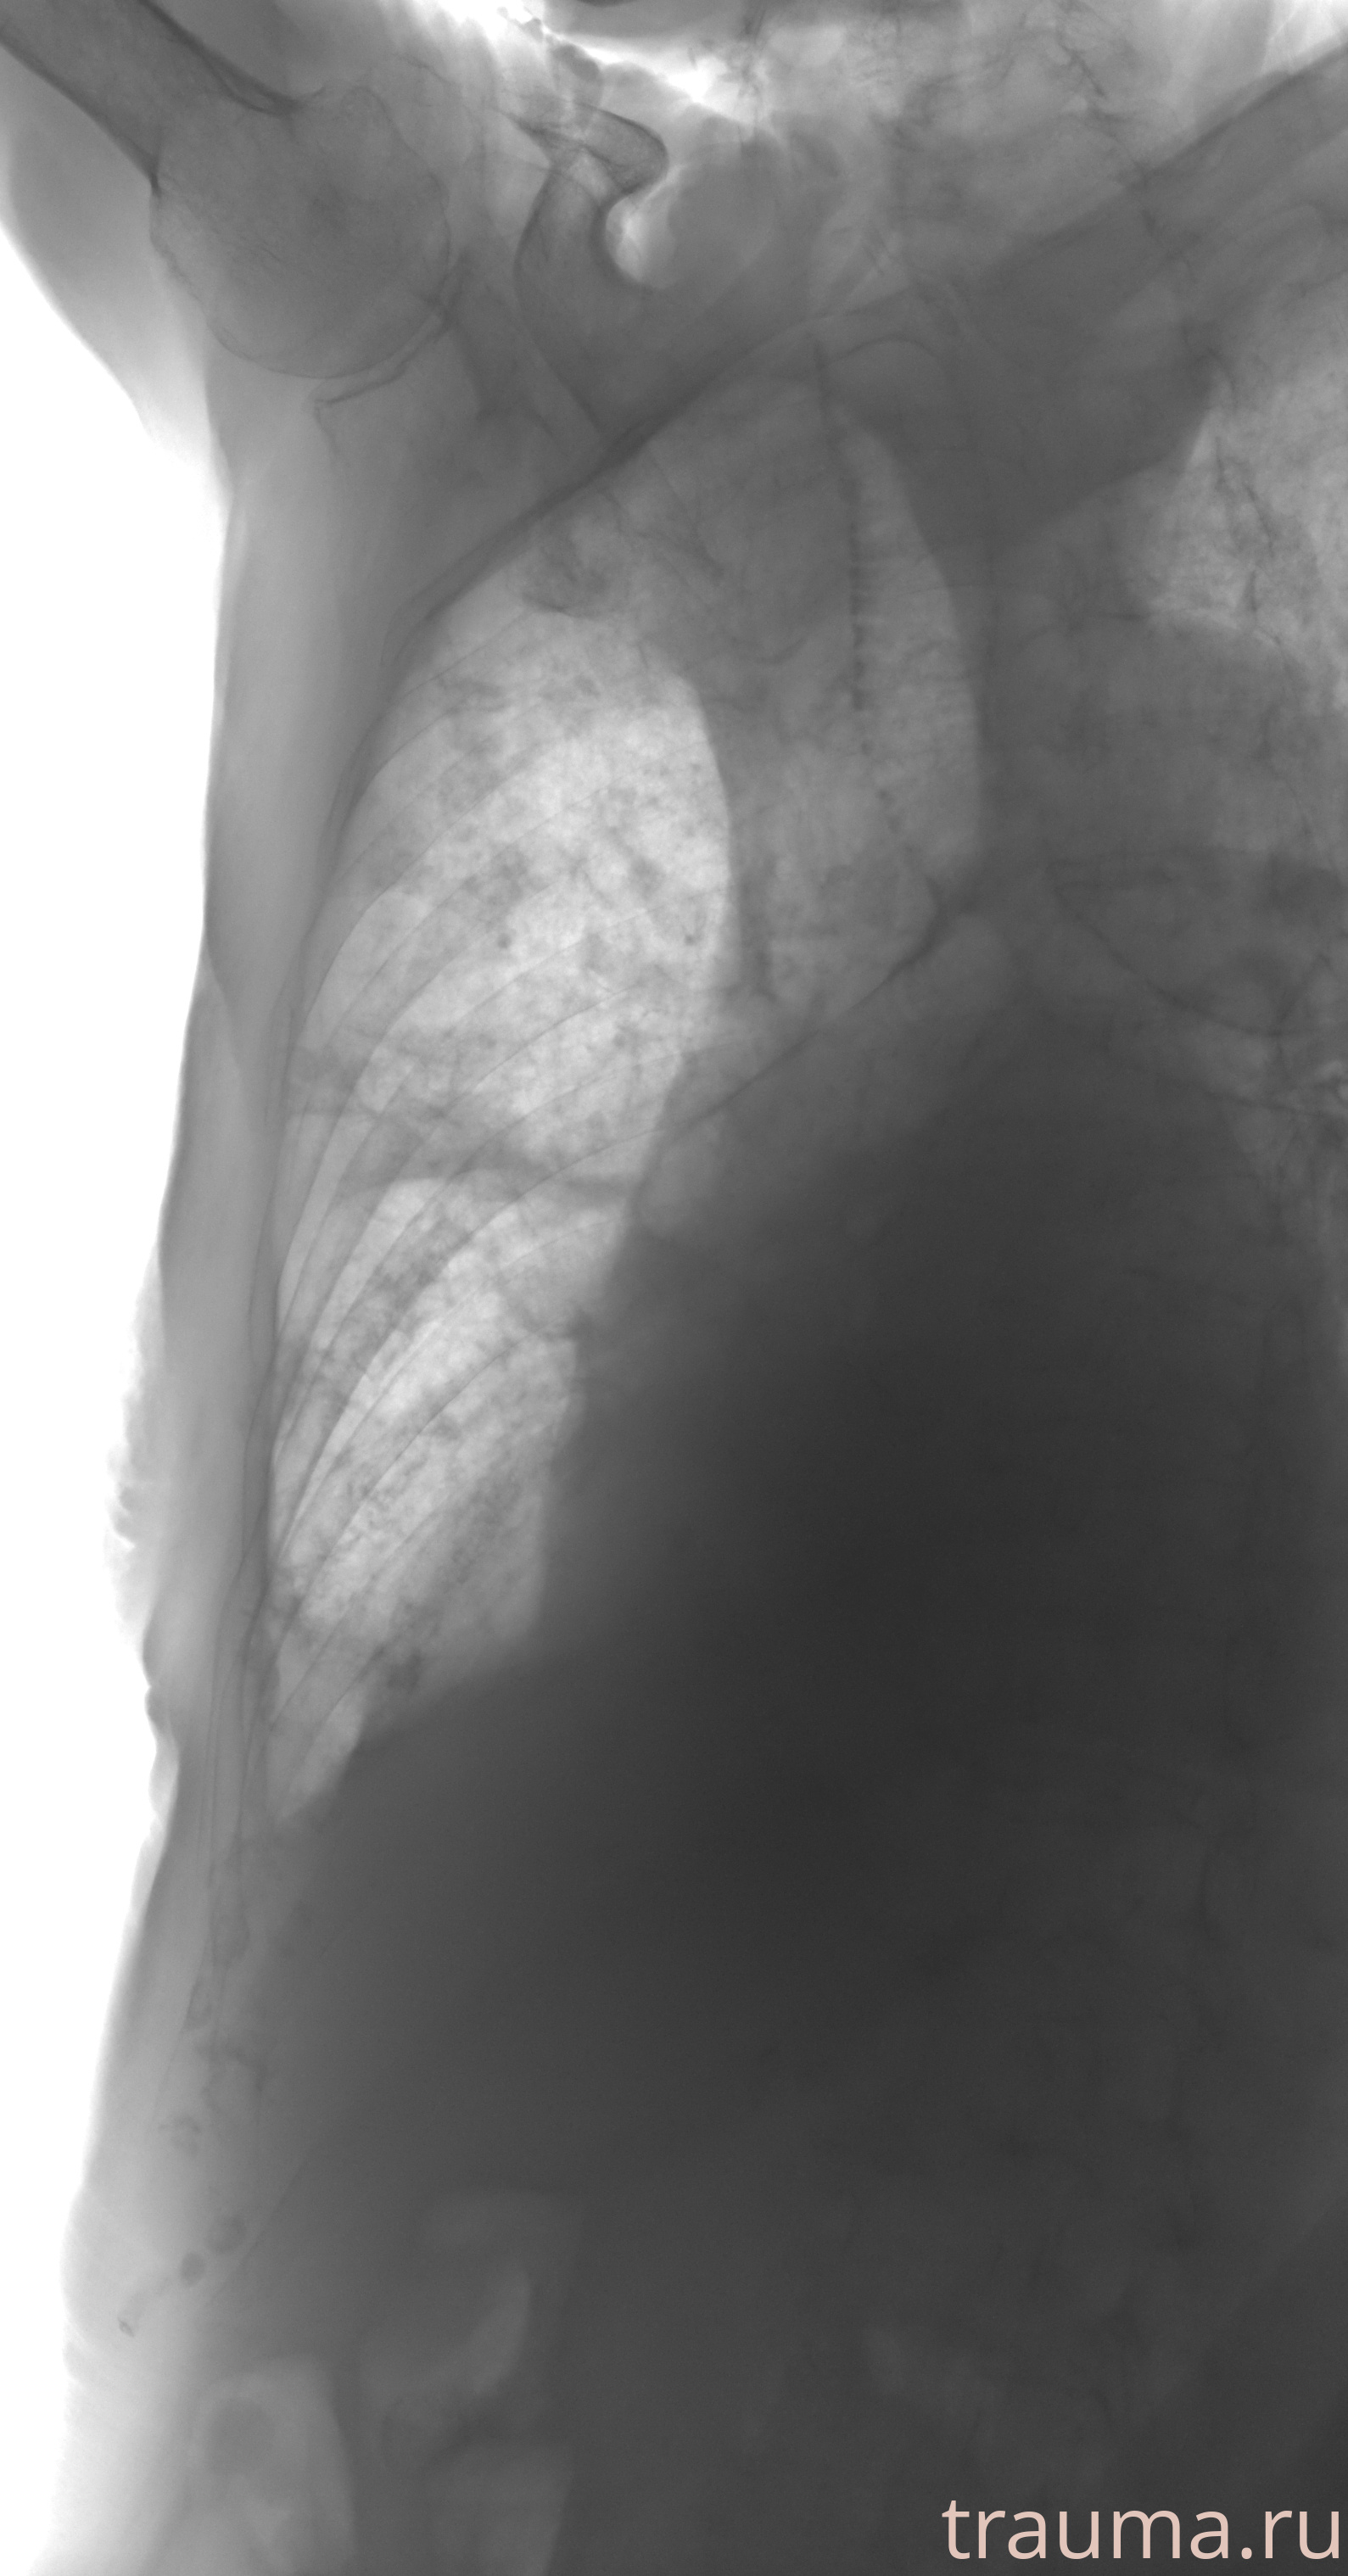

Рентгенограммы

Рентген на дому: по вашему адресу приезжает врач-рентгенолог, травматолог-ортопед с мобильным рентгеновским аппаратом, проводит диагностику травмы или заболевания, делает необходимые рентгенограммы, дает рекомендации по дальнейшему лечению. Получить качественные снимки в домашних условиях возможно благодаря уникальной методике, разработанной МосРентген Центром для института  Склифосовского

при переломе шейки бедра и пневмонии от компании МосРентген Центр - партнера Института имени Склифосовского